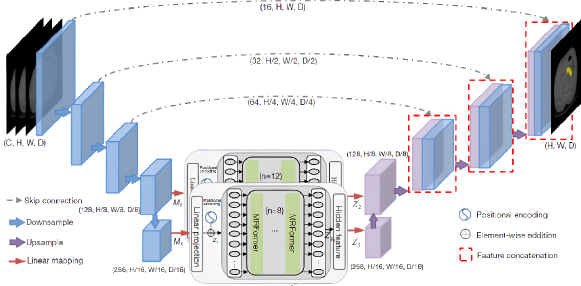

Residual transformer UNet (RTUNet) is a UNet-like network for pancreas parenchyma segmentation with convolutional blocks consisting of residual blocks, residual transformers, and dual convolution down-sampling. The residual transformer block adds progressive up-sampling to the basic transformer (Qiu et al., 2023). UMRFormer-Net is a U-shaped encoder-decoder architecture (Fig. 8) with a hybrid CNN and transformer for segmentation of the pancreatic parenchyma and tumors (Fang et al., 2023). It has five 3D CNN layers and a double transformer module inserted into the bottleneck and skip connection of the fourth layer to encode the long-range dependencies semantic information in a global space (Fang et al., 2023).